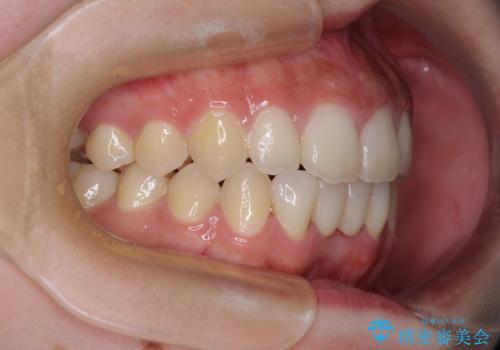

- 下顎前歯に乳歯が残っており、欠損もしていることを気にして来院された患者様です。

舌の突出癖が顕著にあり、上下前歯が非接触となっており、上顎前歯が前方に突出している状態でした。